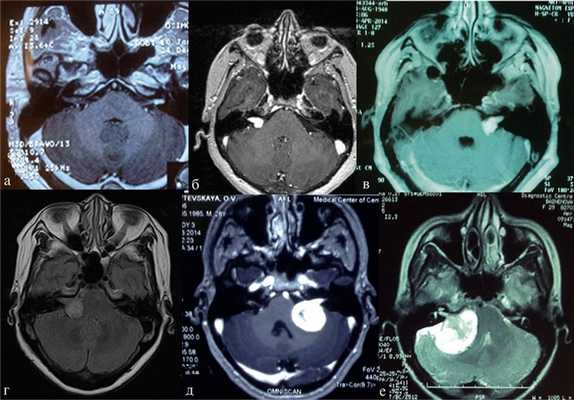

Наиболее информативным методом выявления вестибулярных шванном является МРТ головного мозга с контрастным усилением в режиме Т1 и Т2. Это исследование позволяет определить размеры опухоли, наличие перитуморозного отека, наличие признаков окклюзионной гидроцефалии, которая может быть следствием сдавления опухолью IV желудочка. Кроме этого МРТ позволяет провести дифференциальную диагностику с другими опухолями схожей локализации (чаще с менингиомой задней грани пирамиды височной кости). Еще одним стандартом диагностики является КТ в костном режиме. Независимо от снижения слуха стандартом является проведение аппаратной аудиографии.

Рис. 1.Иллюстрация классификации неврином слухового нерва по Koos. а — I стадия — опухоль находится в пределах внутреннего слухового прохода, диаметр экстраканальной части составляет 1—10 мм; б — II стадия — опухоль вызывает расширение канала внутреннего слухового прохода и выходит в мостомозжечковый угол, ее диаметр составляет, 11—20 мм; в — III стадия — опухоль распространяется до ствола головного мозга без его компрессии, диаметр составляет 21—30 мм; г — IV стадия — опухоль вызывает компрессию ствола головного мозга, ее диаметр более 30 мм.

Рис. 2.Классификация неврином слухового нерва по M. Samii. а — Т1 — интрамеатальная опухоль (рис. 2, a); б —Т2 — интра-экстрамеатальная опухоль; в — Т3а — опухоль заполняет мостомозжечковую цистерну; г —Т3b — опухоль распространяется до ствола головного мозга; д —Т4а — опухоль вызывает компрессию ствола; е —Т4b — опухоль грубо деформирует ствол мозга и IV желудочек.